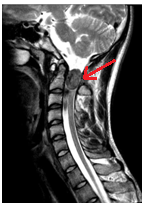

Súlyos trauma a nyaki gerinc: a törés-zavar a C5 csigolya test, súlyos tömörítés az agytörzs, jeleivel gerincvelő-ödéma, a teljes gerinccsatorna szűkület szintjén a törés. MR kép prevertebrális vérömleny.

T1VI T2VI (keverjük) T2VI